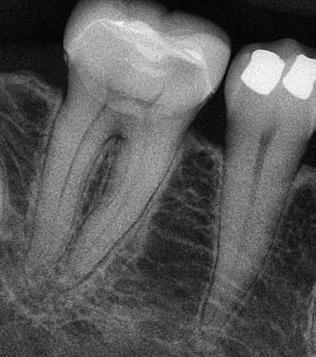

6. a–d. ábrák: A bal alsó második nagyőrlőfogon (3.7) kialakított konzervatív hozzáférési nyíláson keresztül végzett endodonciai kezelés lépései. A mezialis gyökér jelentős mértékben görbült. A gyökértömés hidraulikus kondenzációs technikával készült.

b. ábrák: A jobb alsó első nagyőrlőfogon (4.6) lévő cirkóniumkoronán keresztül elvégzett endodonciai kezelés. A hozzáférési nyílás kialakítása a lehető legkonzervatívabb módon történt. A gyökértömés hidraulikus kondenzációs technikával készült.

egyszerű obturációs technika, az anyag viszkozitási tulajdonságai és a pulpakamra viszonylag egyszerű tisztíthatósága a kezelésünk prognózisának veszélyeztetése nélkül teszi lehetővé az endodonciai beavatkozások lehető legkonzervatívabb módon történő kivitelezését. A bemutatott esetek ellátása során az Aurum Blue rendszert (Meta Biomed) használtuk a gyökércsatornák megmunkálására, míg a gyökértömés elkészítése során hideg hidraulikus kondenzációs technikát alkalmaztunk a kalcium-szilikát alapú CeraSeal (Meta Biomed) sealer felhasználásával (8. ábra).

Esetbemutatás (2., 3.)

Mindkét esetben irreverzibilis pulpitis miatt vált szükségessé a fogak endodonciai kezelése (6. a-d. és 7. a-b. ábrák). Az esetek ellátása során mindvégig minimálinvazív megközelítést alkalmaztunk. A hozzáférési nyílás kialakításától kezdve az endodonciai kezelés befejezését követő csonkfelépítésig, minden beavatkozás ennek megfelelően történt.